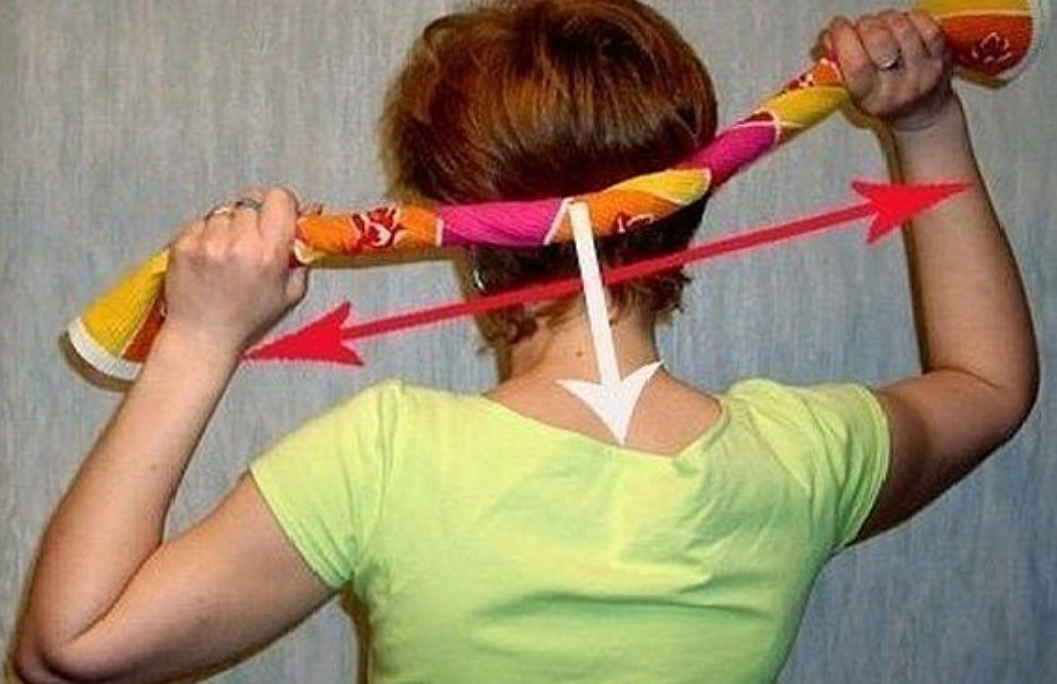

Повторю, безопасным удаление делает не метод, а знания и навыки врача. Пожалуйста, посмотрите еще раз на картинку и постарайтесь ее запомнить.

Наиболее важные и простые правила безопасности я сформулировал на картинке в ответе на предыдущий вопрос.